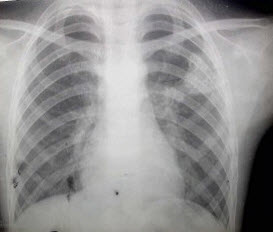

2、单项选择题

男,8岁,高热达38.5℃三天,如图所示,最可能的诊断为()